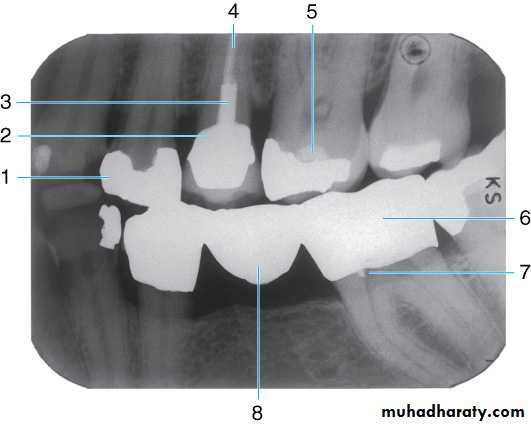

Dental materials. This radiograph shows several metallic and non-metallic dental materials. Since all of the metal restorations are equally radiopaque, their size and shape is observed to determine the type of material. The materials present in this radiograph are: (1) amalgam;(2) porcelain-fused-to-metal crown; (3) post and core; (4) gutta percha; (5) base material; (6) full metal crown, which is the posterior abutment of a three-unit bridge; (7) retention pin; and (8) metal pontic (part of the three-unit bridge).